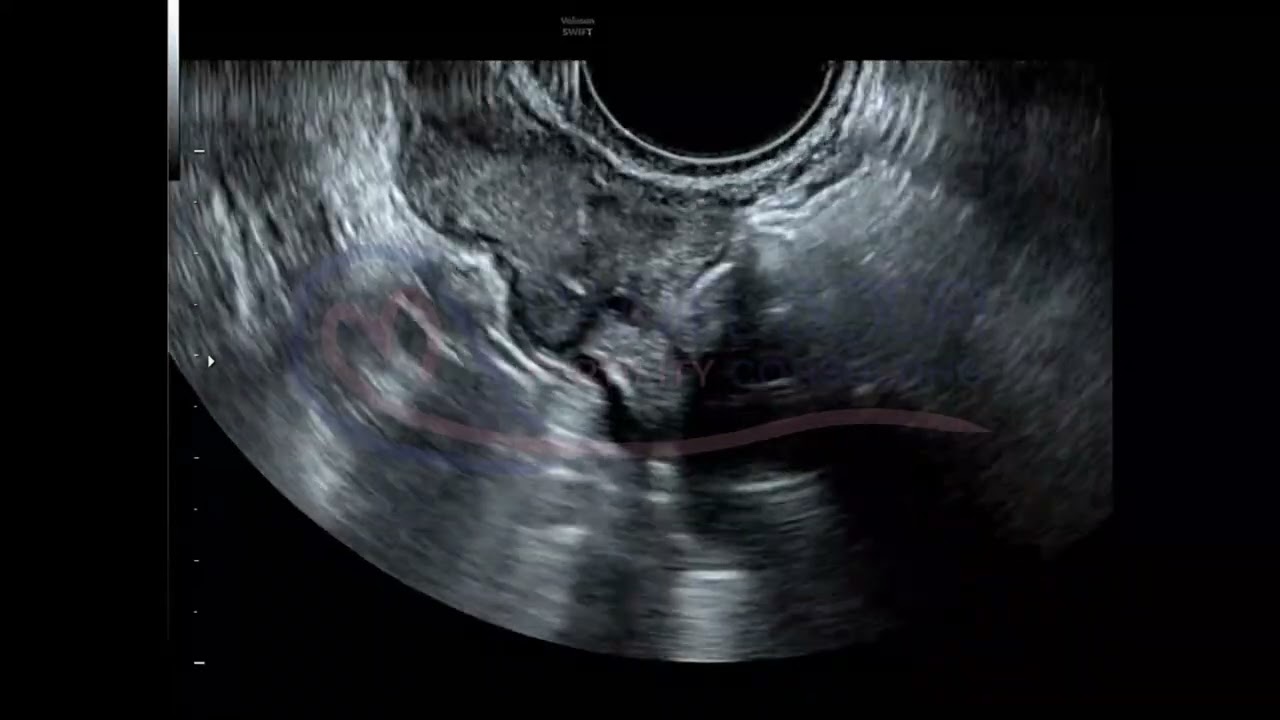

Transvaginal-ultrasound-guided egg collection is a routine procedure during IVF which is performed in the operating theatre under sedation. It usually takes 10-15 minutes during which ovarian follicles are carefully punctured through the vaginal wall with a needle and the follicular liquid is aspirated to harvest an egg from each follicle.